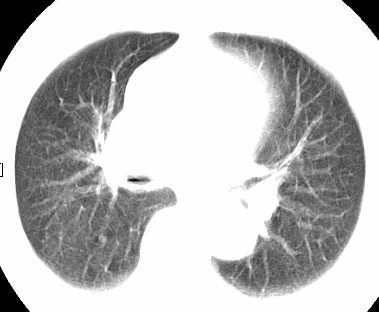

标题: CT26680:肺部右下肺静脉干结节的界定 [打印本页]

标题: CT26680:肺部右下肺静脉干结节的界定

经追查说有支扩咯血病史,但不确定

考虑1、周围型肺癌,2肺静脉畸形,前者可能大,建议增强检查。

考虑1、周围型肺癌,2肺静脉畸形,前者可能大,建议增强检查。支持!

不排除右肺下叶周围型肺癌可能。

中心型肺癌,纤支镜可帮助明确。